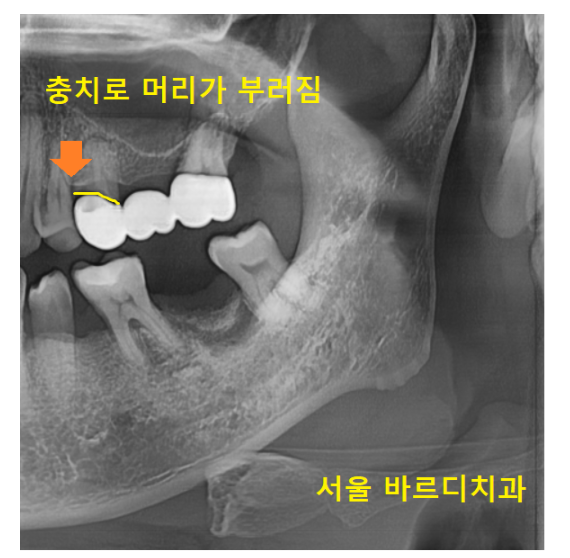

씌워놓았던 치아 1개가 충치가 생겨

머리 부분이 부러졌습니다.

1개 치아에 문제가 생겼지만

브릿지 치료는 다같이 묶어 놓는다는게 제일 큰 문제입니다.

각각 치료한 치아는

문제가 생긴 치아만 건들이면 되지만

브릿지는 통째로 치료를 다시 해야하거든요~

그 얘기는

다른 치아가 문제가 없어도

벗겨내야 한다는 말이에요~!